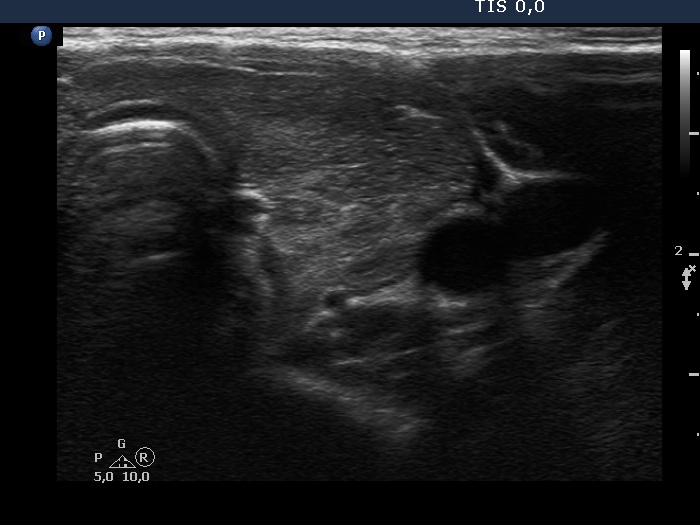

Graves' disease - case 1584

Four years after the first visit (ultrasonographic picture 4)

Right lobe, longitudinal scan

Left lobe, transverse scan. Great part of this lobe became hypoechoic.